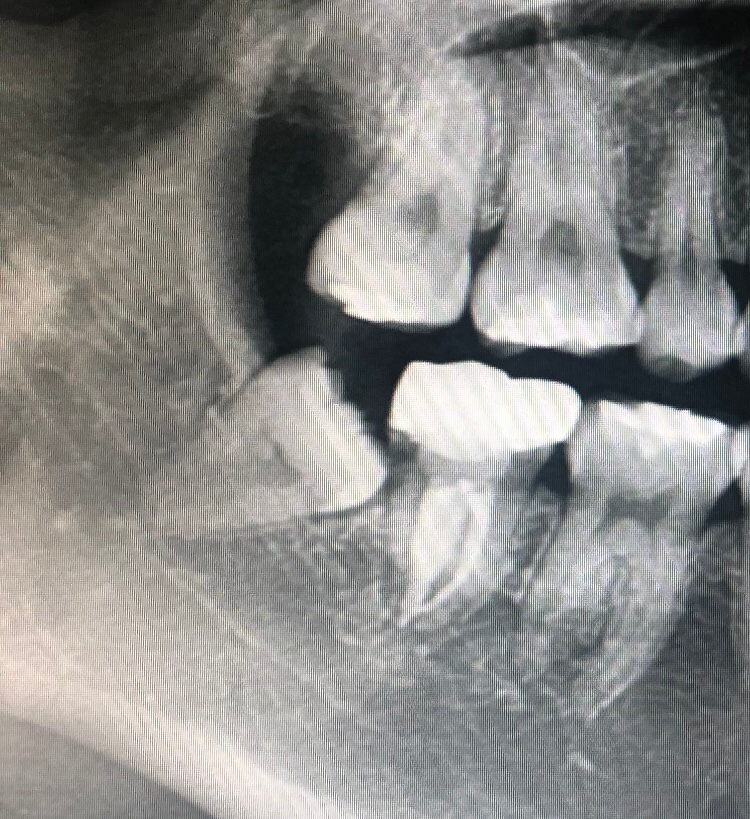

예전에 치과에서 상담받았을때 신경에 닿은건 아니지만 가까이 있기때문에 전문병원 가라는 얘기를 들었었거든요ㅠㅠ 전문병원 기준 매복정도에 따라 발치비용 대충 어느정도쯤인지 알아보고 내원 하고싶어서 질문합니다!

사진 상으로는 완전히 매복되어 있거나 일부 치아 부분의 머리가 보일 것으로 보입니다. 다만 전문 병원 기준으로 매복 정도에 따라 발치 비용이 나오기 보다는 발치 과정에서 어떠한 재료를 추가적으로 사용하는지에 따라 비용이 다를 수 있습니다.

사랑니가 경사져 매복되어 있습니다. 이런 경우 사랑니를 부셔 간단한 수술을 통해 발치해야 합니다.

사진상으로보면 심한 매복은 아닌거 같습니다. 매복사랑니 발치는 의료보험이 적용되지만 지혈제나 CT비용이 청구되면 10만원 내외로 나오실꺼에요.

신경과 가까운 것이 맞으며 대학병원에서 발치를 하시는게 좋습니다. 비용은 대략 10만원 나옵니다.